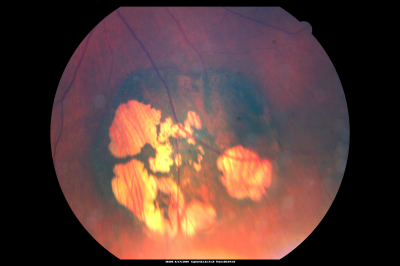

CHRPE lesion in the left eye - Irregular pigmentation

63 year old female with normal vision and CHRPE lesion in the right eye.

Congenital Hypertrophy of the Retinal Pigment Epithelium (CHRPE)

63 year old female also with macular hole